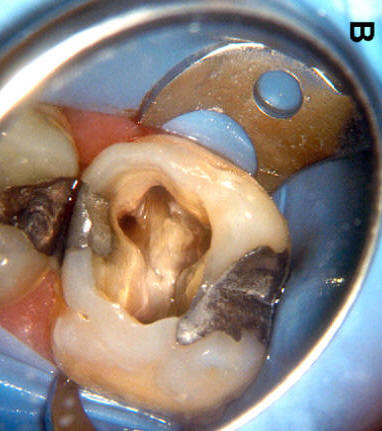

Cuarto conducto en molares superiores (Color amarillo conducto mesio-palatino)

Primer molar superior

Presenta tres raíces, las cuales se distribuyen dos vestibulares y una palatina.

La raíz mesiovestibular es achatada en sentido mesiodistal y amplia en sentido vestibulopalatino.El conducto mesiovestibular con frecuencia es curvo y de sección en forma de hendidura. La existencia de dos conductos en esta raíz, puede presentar la siguiente configuración:

• uno vestibular (Color azul)

• y el otro palatino (Color amarillo)

Estos conductos pueden unirse a distintos niveles, terminando en un foramen único o ser de trayectoria independiente hasta el ápice y terminar en forámenes separados. Son atrésicos y de difícil tratamiento en especial el palatino.

La raíz distovestibular tiene dimensiones menores que la mesiovestibular y no presenta curvaturas acentuadas. El conducto distovestibular (Color verde) por lo general es atrésico y puede presentar curvaturas.

La raíz palatina es la más voluminosa de forma cónica y sección circular. Puede ser recta o curva. Cuando es curva, el sentido e la curva es hacia vestibular. El conducto palatino (Color rojo) es amplio y de fácil acceso, rectilíneo o con una curva leve hacia vestibular.